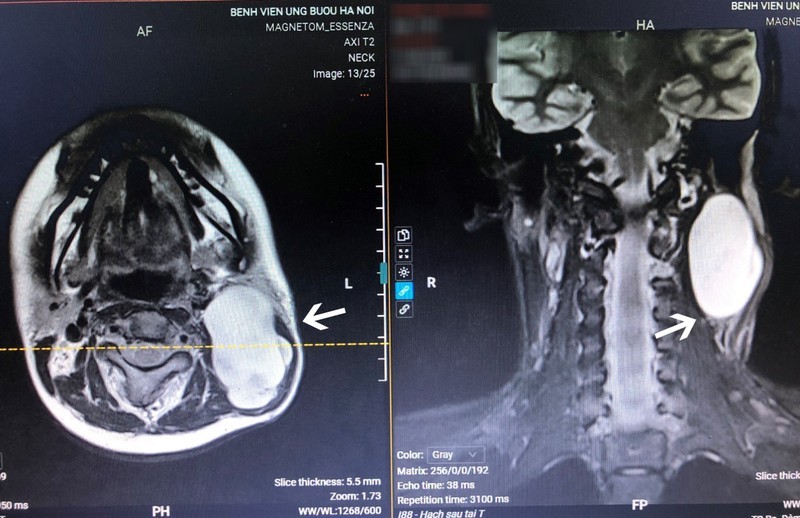

Qua thăm khám và kết quả chẩn đoán hình ảnh, xét nghiệm, các bác sĩ xác định H. mắc bệnh đau xơ thần kinh, một căn bệnh khá hiếm gặp. Trường hợp của H. còn đặc biệt hơn vì vừa có biểu hiện ngoài da, vừa có gốc ở thần kinh trung tâm nên dễ bị chẩn đoán nhầm. Đây cũng là một ca phẫu thuật khó do u có kích thước lên tới 8 cm, xuất phát từ tủy sống, nằm ngay dưới nền sọ, kẹt giữa xương sọ và xương cột sống, gần động tĩnh mạch cảnh nuôi nửa đầu bên trái, khối cơ cổ.

Trước khi mổ, các bác sĩ đã tiến hành chụp cộng hưởng từ đánh giá và hội chẩn kỹ lưỡng, chuẩn bị chi tiết các phương án cầm máu. Phẫu thuật viên phải thực hiện các đường cắt thận trọng đến từng milimet. Cuộc mổ đã diễn ra đúng như dự kiến, khối u được lấy trọn, bệnh nhân mất ít máu nên hồi phục nhanh chóng, vết mổ liền nhanh.